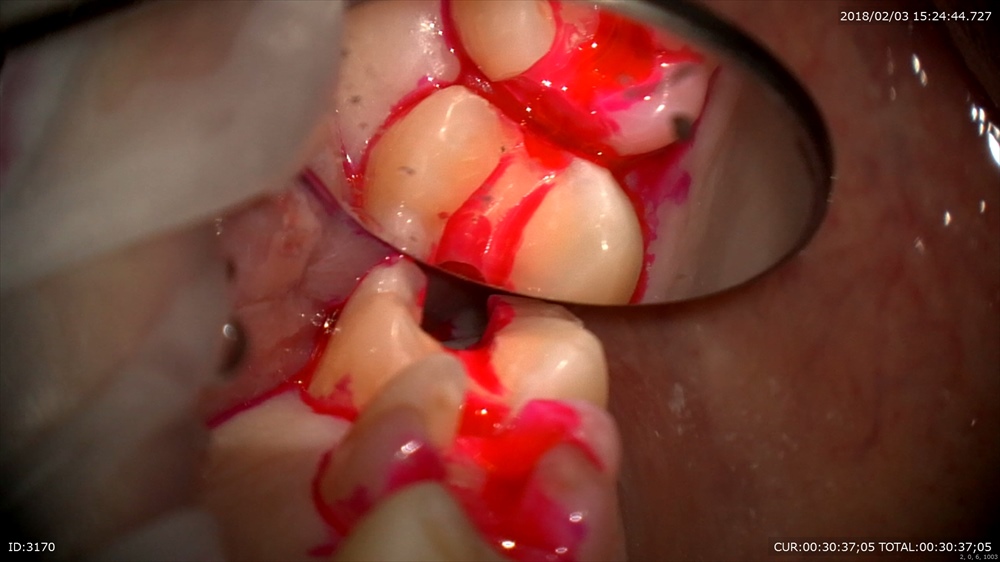

次も虫歯 歯に物がつまる。

これは。

われています。この様に虫歯は「力」によって起こることがあります。

クラック。ヒビがおきてそこから細菌の進入し

このように

大きな虫歯を内部で作ります。だからただ虫歯ができたら詰めるその行為では駄目で原因を探り力のコントロールを行います、そうでないと原因が断ち切れていないので同じ事がおきます。